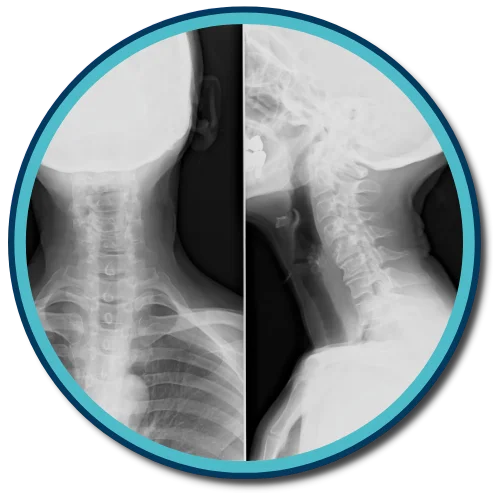

Evergrowth Chiropractic uses the Gonstead method of adjusting and analyzing the spine. We're one of a few offices in Henderson that exclusively uses the Gonstead method. By thoroughly analyzing the spine through the use of x-ray, instrumentation, visualization, static and motion palpation you can expect a properly delivered adjustment.

Adjustments are specific! For instance, the Gonstead technique utilizes a listing system that helps the doctor determine how the misalignment is occurring and the best way to make the correction.

It’s important to adjust the bone in the proper direction in accordance to how the bone is misaligned. It’s of even greater importance that the adjustment reduces and eventually eliminates nerve pressure and restores vital nerve function.